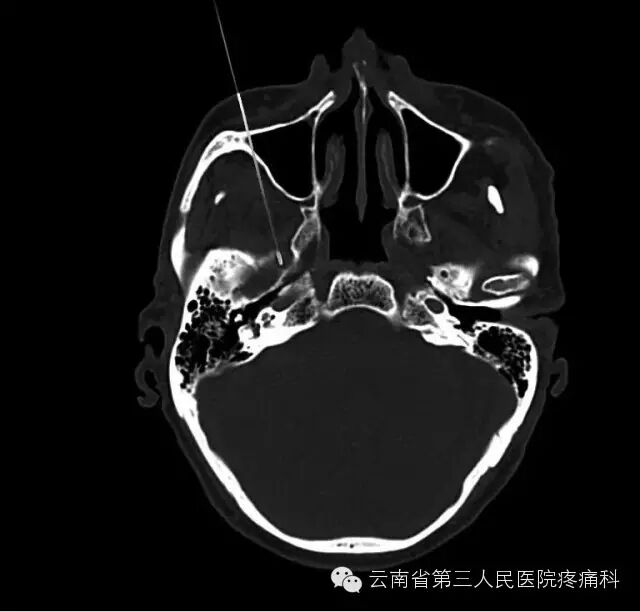

我科熟练开展经卵圆孔半月神经节射频热凝治疗

经皮穿刺半月神经节射频热凝术是治疗三叉神经痛最有效方法之一

治疗原理:三叉神经为感觉神经,其中神经纤维(AA纤维和AB纤维)能耐受较高温度,而痛觉神经纤维不能耐高温,CT引导三叉神经热凝术选择破坏痛觉纤维,使患者疼痛治愈。

治疗优势:安全、疗效好、不易复发、无副作用、费用比手术治疗低、创伤小、痛苦小、治疗时间短。

此项技术的重要环节在于靶点穿刺的准确性,利用CT引导或3维重建技术,可以使穿刺成功率和有效性大大提高。证疗效及安全的另一重要环节为热凝温度选择科学性。